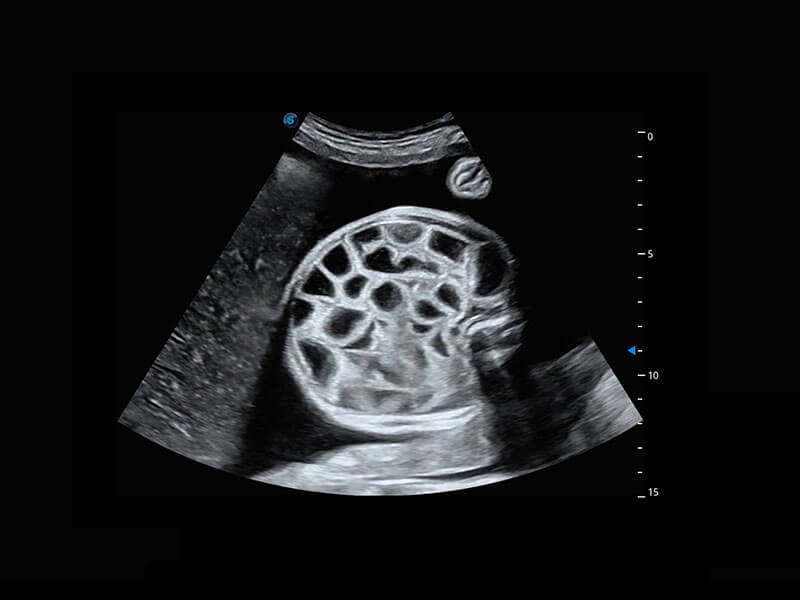

P60搭載一系列胎兒心臟成像技術(shù),實(shí)現(xiàn)精細(xì)的胎兒心臟評(píng)估。

四腔切面

四腔心血流

右室雙出口

胎心容積成像